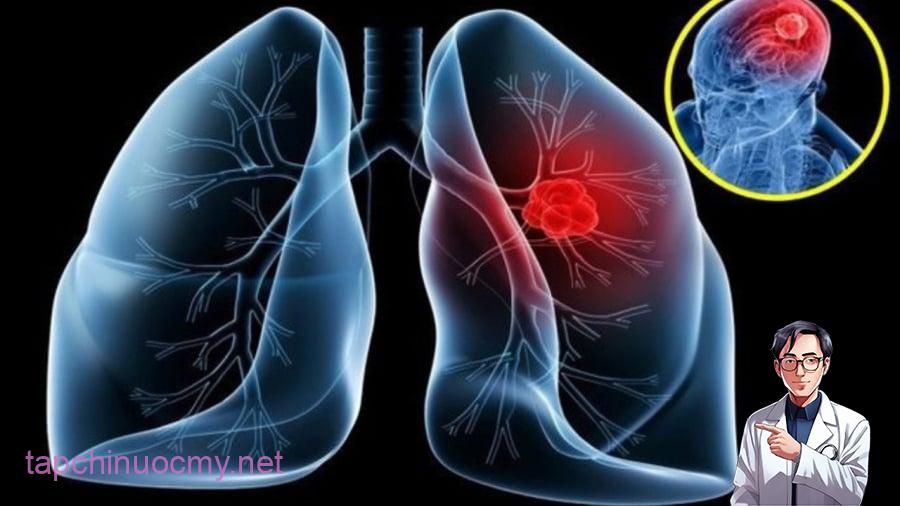

9 dấu hiệu ung thư phổi giai đoạn đầu, đừng lơ là kẻo di căn nguy hiểm

9 dấu hiệu ung thư phổi giai đoạn đầu, đừng lơ là kẻo di căn nguy hiểm

Có tới 70% các bệnh ung thư di căn vào xương. Ung thư phổi di căn đến xương có thể gây ra các triệu chứng đau xương cực độ, giới hạn vận động, cảm giác.

Đau tay, vai và mắt

Một loại ung thư phổi (khối u Pancoast Tobias) thường phát triển ở đỉnh phổi. Ngoài ảnh hưởng đến phổi, những khối u này có thể lan đến xương sườn, đốt sống của cột sống, dây thần kinh hoặc mạch máu, gây đau ở xương bả vai, lưng hoặc cánh tay.

Thậm chí, nó còn ảnh hưởng tới mắt của bạn, khiến bạn cảm giác bị mờ mắt, kèm nhèm, nhức nhối.